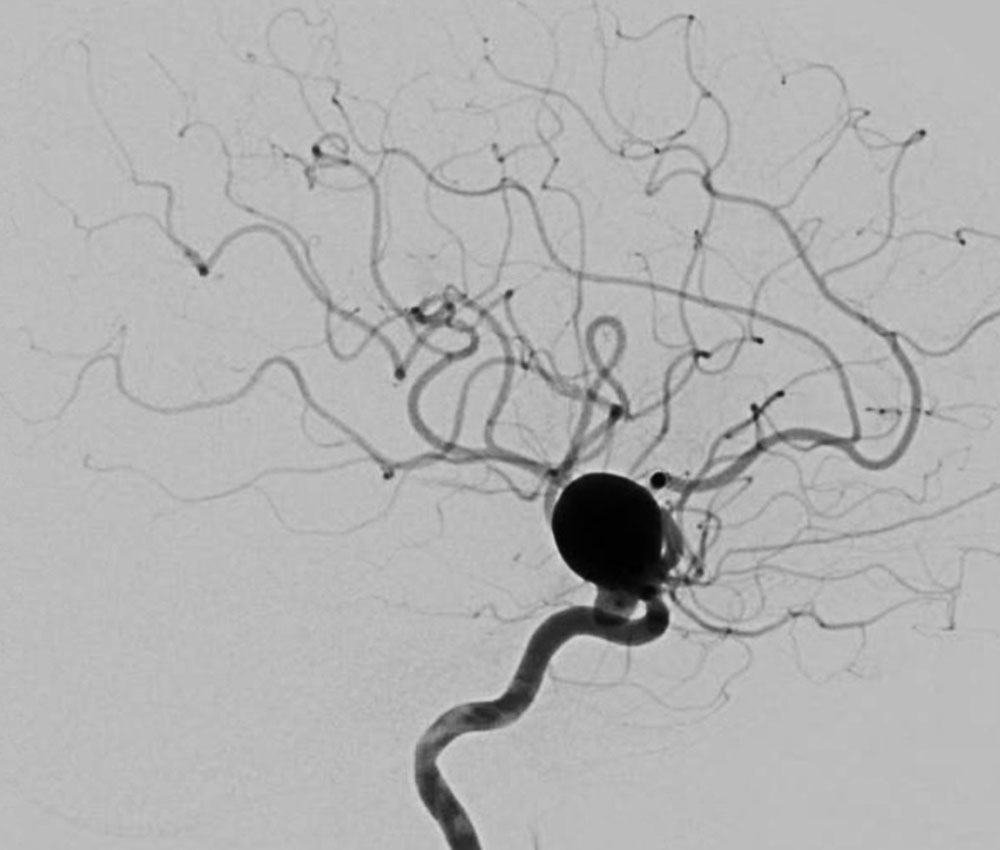

Aneurysma einer Hirnarterie Neurochirurgie Inselspital Bern

from neurochirurgie.insel.ch